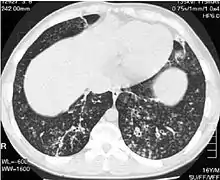

High resolution computed tomography (HRCT) images of the lower chest in a 16-year-old boy initially diagnosed with DPB (left), and 8 weeks later (right) after a 6-week course of treatment with erythromycin. The bilateral bronchiectasis and prominent centri-lobular nodules with a "tree-in-bud" pattern shows noticeable improvement.

The diagnosis of DPB requires analysis of the lungs and bronchiolar tissues, which can require a lung biopsy, or the more preferred high resolution computed tomography (HRCT) scan of the lungs.[7] The diagnostic criteria include severe inflammation in all layers of the respiratory bronchioles and lung tissue lesions that appear as nodules within the terminal and respiratory bronchioles in both lungs.[4] The nodules in DPB appear as opaque lumps when viewed on X-rays of the lung, and can cause airway obstruction, which is evaluated by a pulmonary function test, or PFT.[6] Lung X-rays can also reveal dilation of the bronchiolar passages, another sign of DPB. HRCT scans often show blockages of some bronchiolar passages with mucus, which is referred to as the "tree-in-bud" pattern.[7] Hypoxemia, another sign of breathing difficulty, is revealed by measuring the oxygen and carbon dioxide content of the blood, using a blood test called arterial blood gas. Other findings observed with DPB include the proliferation of lymphocytes (white blood cells that fight infection), neutrophils, and foamy histiocytes (tissue macrophages) in the lung lining. Bacteria such as H. influenzae and P. aeruginosa are also detectable, with the latter becoming more prominent as the disease progresses.[4][5] The white blood, bacterial and other cellular content of the blood can be measured by taking a complete blood count (CBC). Elevated levels of IgG and IgA (classes of immunoglobulins) may be seen, as well as the presence of rheumatoid factor (an indicator of autoimmunity). Hemagglutination, a clumping of red blood cells in response to the presence of antibodies in the blood, may also occur. Neutrophils, beta-defensins, leukotrienes, and chemokines can also be detected in bronchoalveolar lavage fluid injected then removed from the bronchiolar airways of individuals with DPB, for evaluation.[4][9]